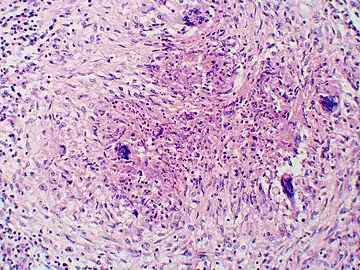

Granuloma with early suppuration. Fungal organisms difficult to recognize at this low magnification.

Once suspected, the diagnosis of blastomycosis can usually be confirmed by demonstration of the characteristic broad based budding organisms in sputum or tissues by KOH prep, cytology, or histology.[27] Tissue biopsy of skin or other organs may be required in order to diagnose extra-pulmonary disease. Blastomycosis is histologically associated with granulomatous nodules.